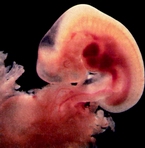

"От този момент нататък във вас живее не просто „яйце“, а ембрион. От образувалите се три зародишни пласта, започват да се формират определени органи и системи. От вътрешния пласт (ендодерма) се оформят белите дробове, черният дроб, храносмилателната система, задстомашните жлези. От средния (мезодерма) - се развива опорнодвигателната система: скелетът и мускулите, както и бъбреците, кръвоносните съдове и сърцето. От външния пласт (ектодерма) се образуват кожата, косата, очите, зъбите, нервната система. По-късно клетките на всеки пласт „отиват по местата си“. Образува се главата на ембриона. Интересното е, че точно в този момент от развитието си ембрионите на всички бозайници си приличат - те представляват миниатюрна дъгичка с капковидна глава и опашка. |

На този етап зародишът е потънал напълно в лигавицата на матката. Той е минал първия критичен период на имплантацията: сега не само носите зародиш, вие вече сте свързани с него.

За четирите седмици ембрионът е увеличил размера си приблизително 10 000 пъти от момента на оплождането.

Вече започват да се оформят лицето, очните ябълки, очертава се долната челюст и шията на бебето. Появява се кръвообращение."